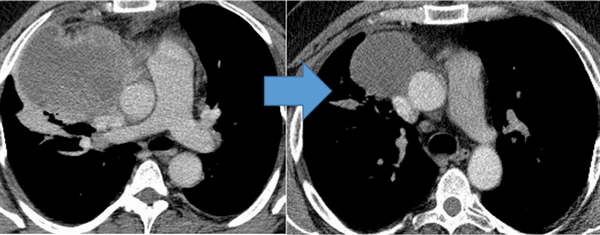

Средостение

В средостении в большинстве случаев присутствуют крупные опухоли, но при этом синдром сдавления верхней полой вены диагностируется редко.

Рисунок 6. — КТ органов грудной клетки - семинома средостения.

Гистологическая картина новообразования в основном смешанного происхождения, имеет тератоидный компонент и клетки, которые характерны для новообразования желточного мешка.

![]()

Когда опухоль располагается в средостении, особенности при ее больших размерах, пациента будут беспокоить жалобы на кашель, одышку, боли в груди, невозможность выполнять без усилия привычную физическую активность, возможна отечность шеи, синюшность кожных покровов.

Могут возникать шум в голове/ушах, ухудшение зрения, головная боль, сонливость. Это объясняется тем, что растущая опухоль давит на верхнюю полую вену.

Химиотерапия

Показания к химиотерапии определяются степенью распространенности процесса, наличием легочных/внелегочных метастазов. Стандартным режимом химиотерапии при герминогенных опухолях является режим «BEP», включающий блеомицин, этопозид и цисплатин. Для пациентов с дыхательной недостаточностью, обширным поражением легких, во избежание легочной блеомициновой токсичности, как альтернативный вариант, может быть использованы режимы химиотерапии VIP (этопозид, ифосфамид, цисплатин) или ЕР (этопозид, цисплатин).

Для оценки эффективности химиотерапии каждые 2 цикла и после ее окончания проводится компьютерная томография исходных зон поражения, перед каждым циклом мониторинг уровня опухолевых маркеров. Рост маркеров на фоне лечения или после его завершения, а также замедление их снижения свидетельствует об активности опухолевого процесса и необходимости проведения второй линии химиотерапии.

![Герминогенная опухоль средостения до лечения и после 4х циклов химиотерапии по схеме «ВЕР » - уменьшение опухоли более чем на 50% (КТ грудной клетки).]()

Герминогенная опухоль средостения до лечения и после 4х циклов химиотерапии по схеме «ВЕР » — уменьшение опухоли более чем на 50% (КТ грудной клетки)